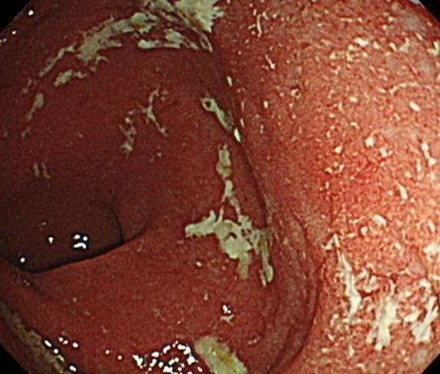

潰瘍性大腸炎(Ulcerative Colitis:UC)

潰瘍性大腸炎

特に直腸に慢性の炎症が起こり

粘膜に潰瘍や出血をきたします

潰瘍性大腸炎の診断には、大腸内視鏡検査が欠かせません。炎症の範囲により、「直腸炎型」「左側大腸炎型」「全大腸炎型」のように分類します。炎症は多くの場合、直腸から始まり、徐々に口側の腸の奥に広がっていくと考えられています。

腸内の炎症の範囲や状態を直接確認し、必要に応じて粘膜の一部を採取して病理検査を行います。